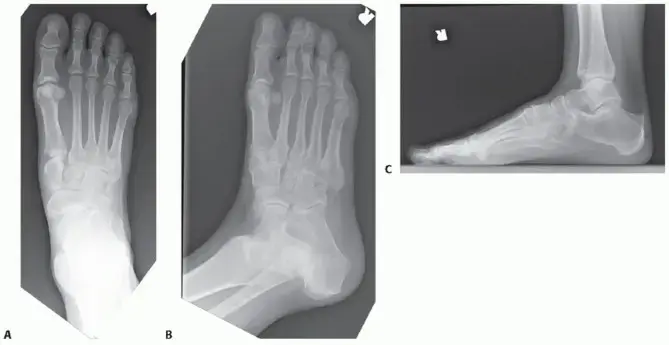

لفهم عملية دمج منتصف القدم، دعونا نلقي نظرة سريعة وبسيطة على تشريح هذه المنطقة الحيوية من القدم. تخيل قدمك مقسمة إلى ثلاثة أجزاء رئيسية: القدم الخلفية (الكاحل والكعب)، منتصف القدم، ومقدمة القدم (الأصابع).

منتصف القدم هي المنطقة الوسطى، وتعتبر جسرًا حيويًا بين القدم الخلفية ومقدمة القدم. تتكون هذه المنطقة من عدة عظام صغيرة ومفاصل معقدة، تعمل معًا لامتصاص الصدمات، توزيع الوزن، والحفاظ على شكل القوس الطبيعي للقدم.

العظام والمفاصل الرئيسية في منتصف القدم

• العظام الرسغية (Tarsals): مثل العظم الزورقي والعظام الإسفينية (المسماة أيضًا الوتدية)، والعظم المكعبي.

• عظام الأمشاط (Metatarsals): هي العظام الطويلة التي تتصل بالأصابع.

المفاصل الرئيسية في منتصف القدم تشمل:

* مفاصل رسغية مشطية (Tarsometatarsal - TMT): وهي المفاصل التي تربط العظام الرسغية بعظام الأمشاط.

* مفاصل زورقية إسفينية (Naviculocuneiform): تربط العظم الزورقي بالعظام الإسفينية.

تُشكل هذه العظام والمفاصل أقواسًا طبيعية في القدم – قوس طولي وقوس عرضي. هذه الأقواس ليست مجرد منحنيات في القدم، بل هي هياكل هندسية رائعة تعمل كـ "نوابض" لامتصاص الصدمات عند المشي أو الجري، وتوزيع الضغط بالتساوي.